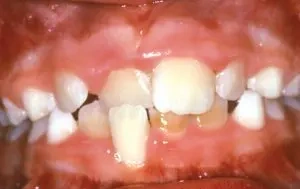

Crowding

Crowding occurs when teeth have insufficient room to erupt from the gum. Crowding can often be corrected by expansion, and many times, tooth removal can be avoided.